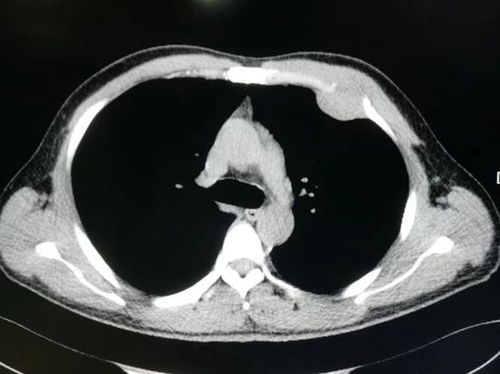

在面对1cm的肾肿瘤时,大多数情况下,尤其是当肿瘤边界清晰且无明显临床症状时,良性的可能性较高,如肾囊肿或错构瘤。即使在这种情况下,我们也不能完全排除约10%-30%的可能是早期恶性病变,如肾透明细胞癌。为了精确判断其性质,增强CT或MRI检查是必要的。